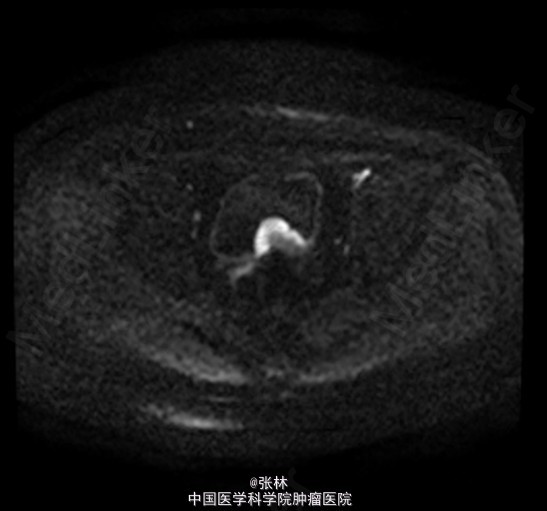

CT:膀胱充盈尚可,内见积气、气液平面;膀胱后壁明显不规则增厚,形成肿物,边界不清,范围约4.8×2.8cm,膀胱壁外缘毛糙,局部与直肠前壁分界不清。考虑:膀胱后壁肿物,与直肠关系密切,考虑为恶性。 MR:膀胱左后壁肿物,与精囊腺及后方直肠分界不清,膀胱充盈状态不同,形态较前改变,现范围约3.6×4.2cm,边界不清楚,T1WI呈低信号,T2/FS呈高信号,DWI扩散受限,增强扫描呈明显不均匀强化,考虑为恶性。